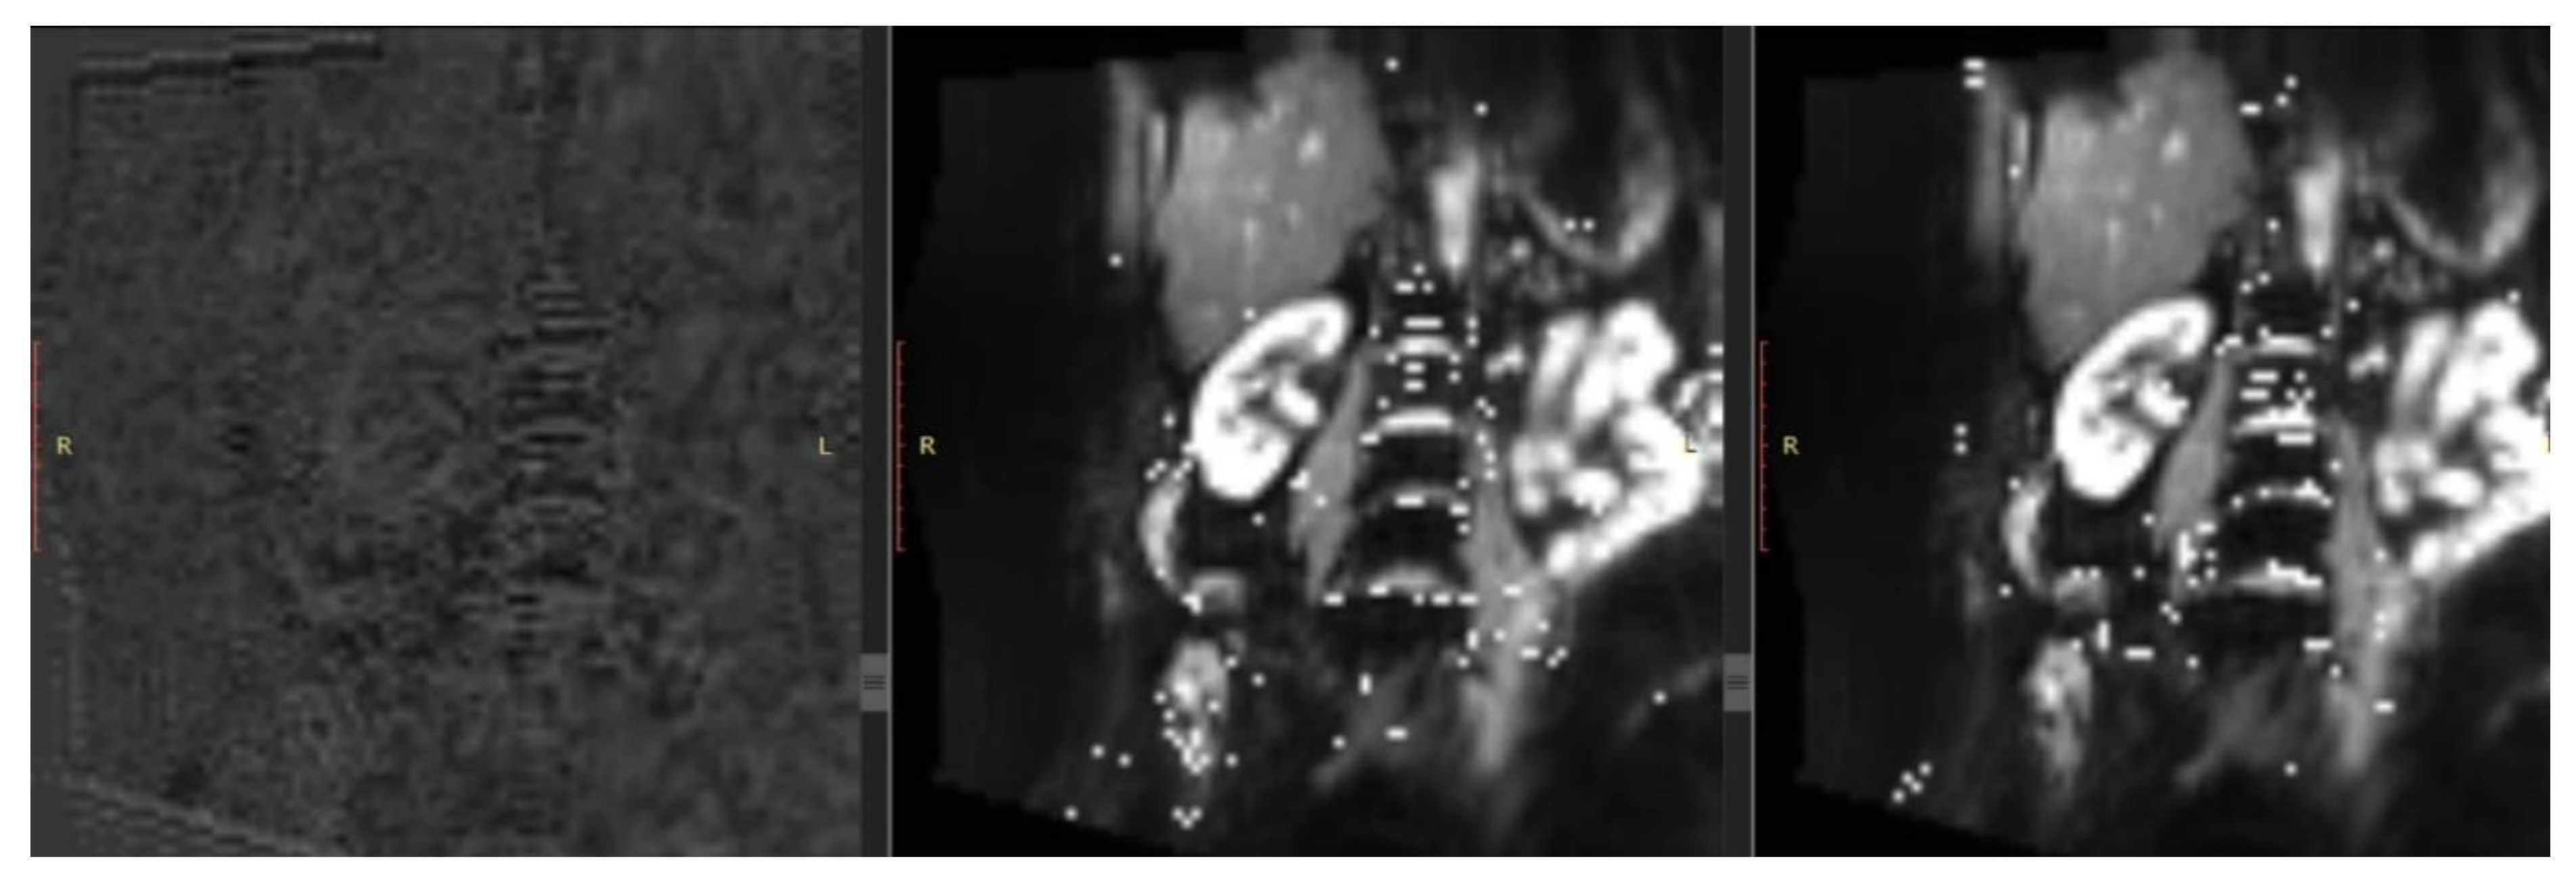

- Le Bihan, D.; Iima, M. Diffusion Magnetic Resonance Imaging: What Water Tells Us about Biological Tissues. PLOS Biol. 2015, 13, e1002203. [CrossRef]

- Liu, Z.; Xu, Y.; Zhang, J.; Zhen, J.; Wang, R.; Cai, S.; Yuan, X.; Liu, Q. Chronic kidney disease: pathological and functional assessment with diffusion tensor imaging at 3T MR. Eur. Radiol. 2015, 25, 652–660. [CrossRef]

- Zhou, H.Y.; Chen, T.W.; Zhang, X.M. Functional Magnetic Resonance Imaging in Acute Kidney Injury: Present Status. Biomed Res. Int. 2016, 2016. [CrossRef]